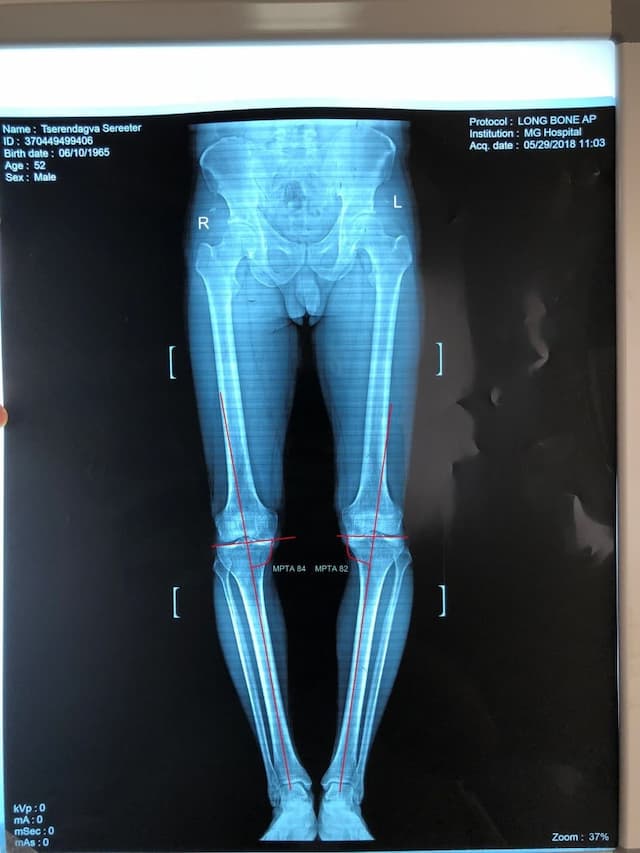

Биеийн жингийн шугамыг мэс заслын өмнө болон мэс заслын дараа хэмжсэн байдал

Шаантны дотор дээд өнцөг мэс заслын өмнө баруун хөлд 84o, зүүн хөлд 82o байсан бол мэс заслын дар аа баруун хөлд 96o, зүүн хөлд 94o болж засагдсан байдал.